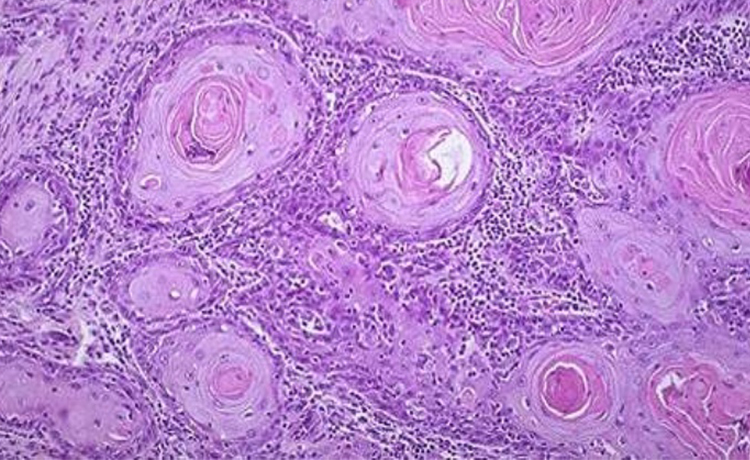

Penis kanseri hem penis üzerinde hem de içerisinde gelişebilen bir kanserdir. En yaygın penis kanseri, deri hücreleri üzerinde ortaya çıkar. Skuamöz (yassı) hücrelerde görülen kanser, genellikle penis ucunda ya da gövdesinde görülür. Skuamöz hücreli kanserler, yavaş yayılan ve çoğunlukla erken evrelerde tespit edilen kanserlerdir. Erken teşhis edilebilen kanser, tedaviye de hızlı bir şekilde yanıt verir.

Penis kanseri; Penis ve penis çevresinde yer alan erkek cinsel organlarının (testis gibi) etkilendiği bir kanser türüdür. Cinsel organlarda görülen kanser türleri arasında en az görülen kanserin penis kanseri olduğu bilinmektedir. Penis kanseri, cilt dokusunda ya da penis içerisinde gelişir. Peniste bulunan hücrelerin kontrolsüz bir şekilde büyümesi ve sağlıklı hücreleri baskılaması, penis kanserinin oluşmasına neden olmaktadır. Kanserin ortaya çıkma nedeni tam olarak tespit edilemese de sünnetsiz olmak, HIV taşıyıcısı olmak gibi risk faktörlerinin önemli oranda etkili olduğu görülmüştür. Yaygın olarak deri üzerinde bulunan yassı (skuamöz) hücrelerde kanserleşme görülür. Penisin cilt yüzeyinde gelişen kanserlere, cinsel organ cilt kanseri de denebilmektedir.